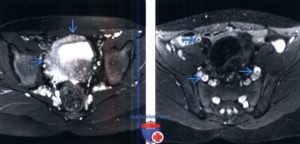

Мужчина, 49 лет, уротелиальная карцинома.

а) Т2-взвешенное изображение показывает опухоль с тканевой интенсивностью МР-сигнала на заднее-левой стенке мочевого пузыря.

При этом видно легкое повышение интенсивности МР-сигнала от гипоинтенсивной в норме стенки пузыря (стрелки).

(б Диффузинно-взвешенное изобрежение показывает опухоль (тонка стрелка) и ее распространение в подслизистый слой (головки стрелок), без признаков инвазии в мышечный слой.

Инвазивная уротелиальная карцинома

а)Т2-tra б) Т1-sag в)Т2-диффузия (DW)

Мужчина, 72 года. В заднее-левых отделах мочевого пузыря визуализирвется объемное образование (уротелиальная карцинома), стадия 3b.

(а) Аксиальное T2-взвешенное изображение показывает больших размеров опухоль с инвазией мышечной стенки и развитием гидроуретера (стрелка). Видна инвазия мышечного слоя, но достовено судисть о паравезикальном распространении невозможно.

(б) Динамическое контрастирование на скане, проходящем перпендикулярно к основанию опухоли выявляет тотальное поражение стенки пузыря, нечеткость заднего контура опухоли.

(в) Поперечное диффузионно-взвешенное изображение демонстрирует большую опухоль с признаками трансмурального роста и инвазии в паравезикальную клетчатку (стрелка).